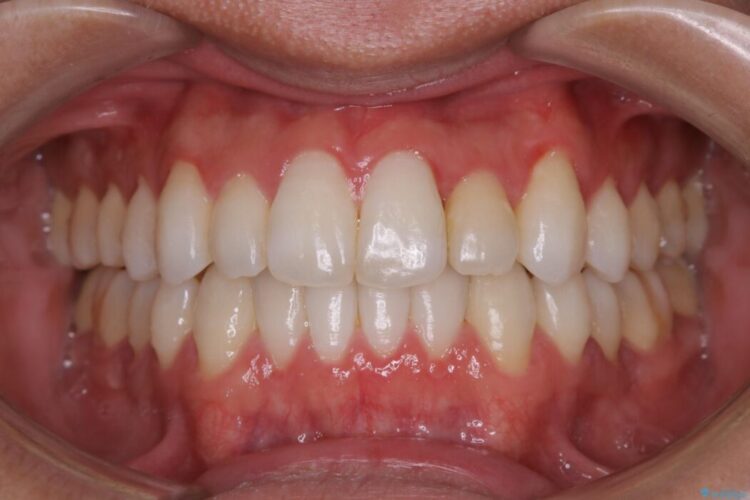

治療後について

前に出ていた前歯や目立つ八重歯(3番目の歯)もきれいに並び、奥歯の虫歯治療も並行して行ったため、機能面でも見た目的にも良くなり満足していただきました。